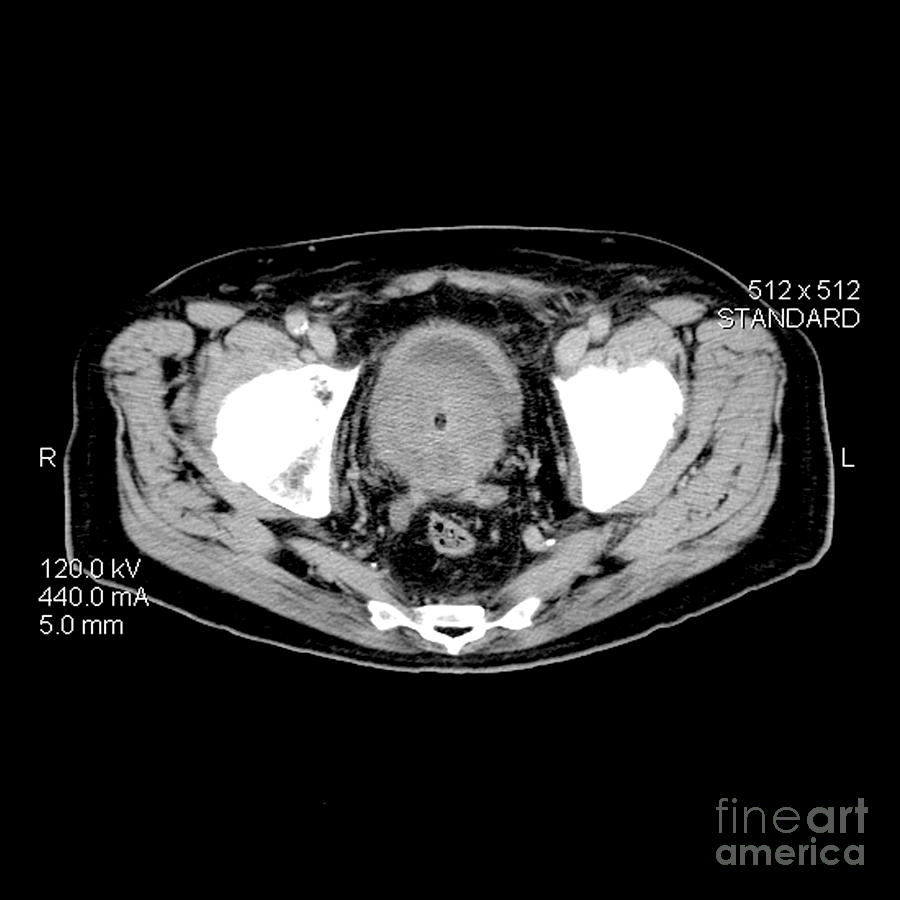

Ct Prostate Cancer Photograph by Medical Body Scans

Ct Prostate Cancer Photograph by Medical Body Scans

Prostate cancer: CT findings | Eurorad